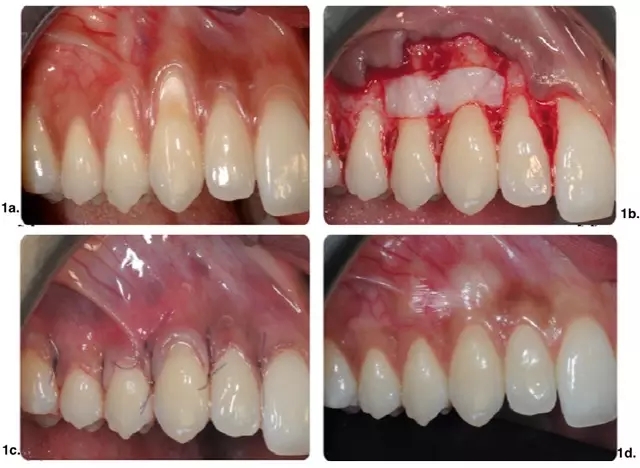

皮瓣設計無垂直切口治療多顆牙牙齦萎縮。實驗組手術(shù)及術(shù)后效果如圖 1 所示,CTG(涉及至少 2 個相鄰牙的牙齦萎縮)應用在有張力區(qū)域。對照組僅使用 CAF(圖 2)。

圖 1.CAF+CTG 手術(shù)示意圖。